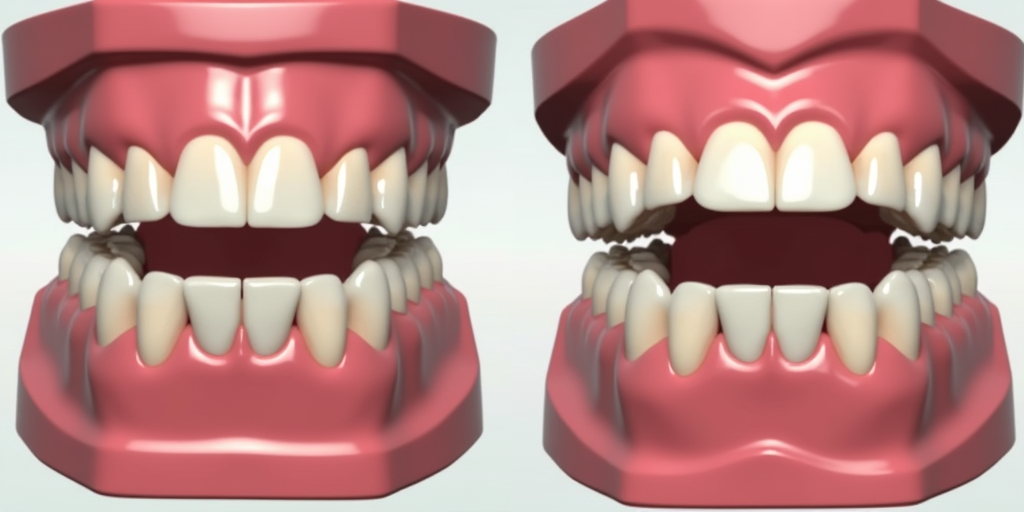

① 数字化种植牙:利用CBCT影像和3D导板稳准定位种植体

② 即刻负重技术:种植后当天佩戴临时牙冠,缩短治疗周期

① GBR骨引导技术:促进骨组织再生

② 即刻负重技术:种植体植入后立即加载咬合

③ 数字化导航:误差控制在0.2mm以内

1、技术优势

① 德国海德堡大学技术引进:数字化方案设计精度达98%

② 即刻负重技术:较传统方案缩短60%治疗周期

③ 全息影像系统:可模拟10年后的咬合变化